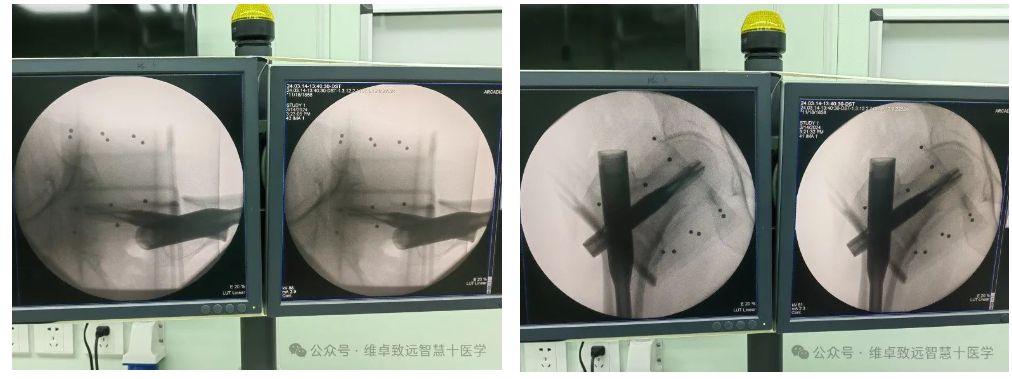

予右腕部手法复位后,建议手术,后转入解放军总医院海南医院治疗。由骨科主任林峰带领团队综合评估后,决定在导航系统的辅助下,进行股骨粗隆间骨折内固定术。 手术中医生在导航的精确引导下,近端切口仅4厘米,术中主钉导针及螺旋刀片导针均一次性置入,体现了手术的微创性、精准性。使用术中C臂机进行透视仅有13次,减少了医生及患者的射线辐射总量。手术过程非常顺利,患者术后良好。这一案例的成功,充分展示了导航手术在骨科领域的优势和应用前景。

导航在手术中应用及验证